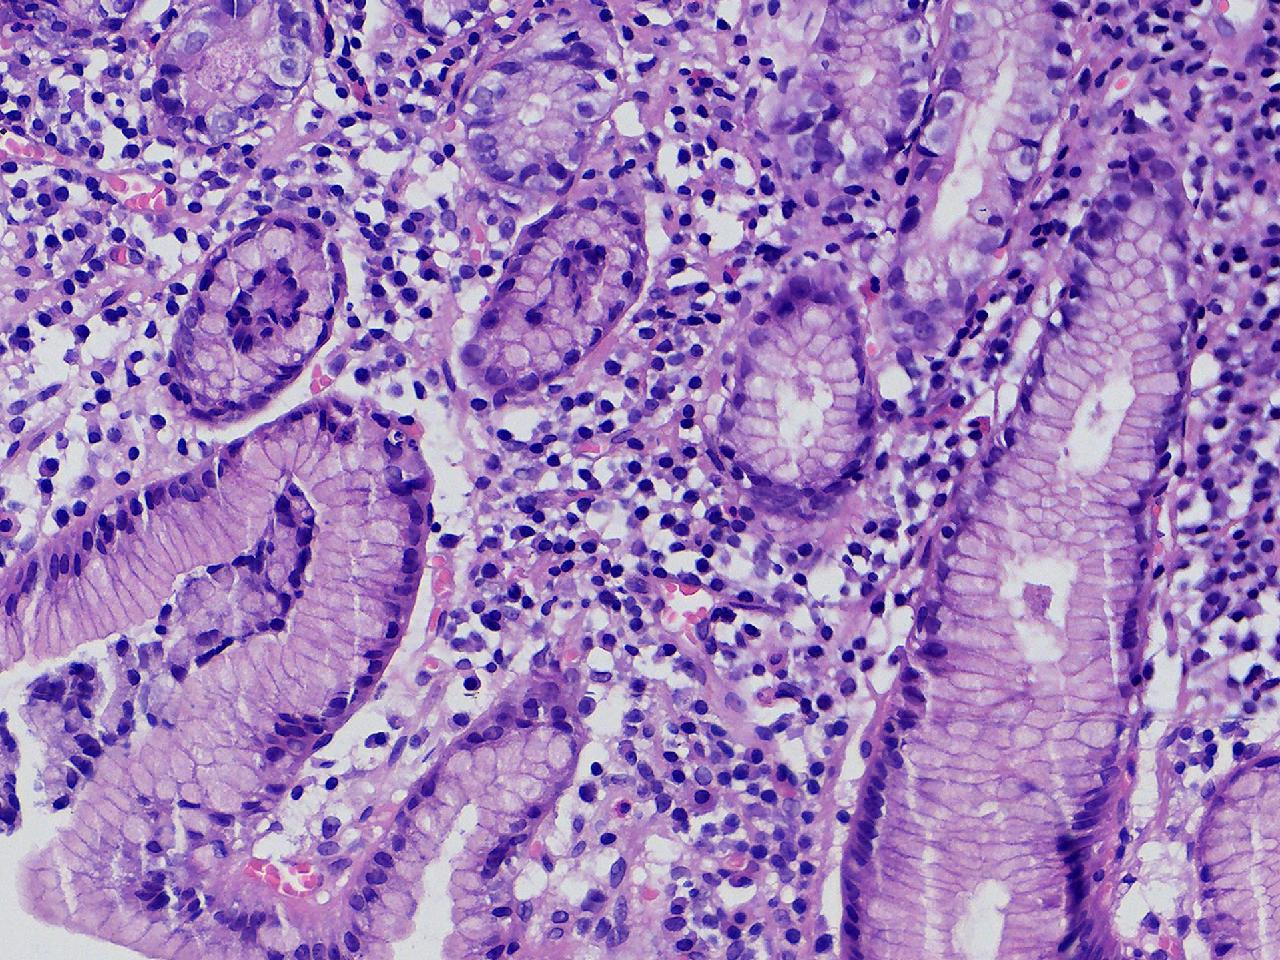

间质内是炎细胞吗?

男,49岁,胃镜活检,胃窦粘膜红白相间,以红为主,后壁见一直径约0.4cm大小片平隆起,表面糜烂,活检1块送检,质软弹性可。

胃窦活检

灰白色不整形软组织1块,直径0.2厘米。

是!还有组织细胞

幽门型粘膜中度慢性炎

是的,主要是淋巴细胞和浆细胞。